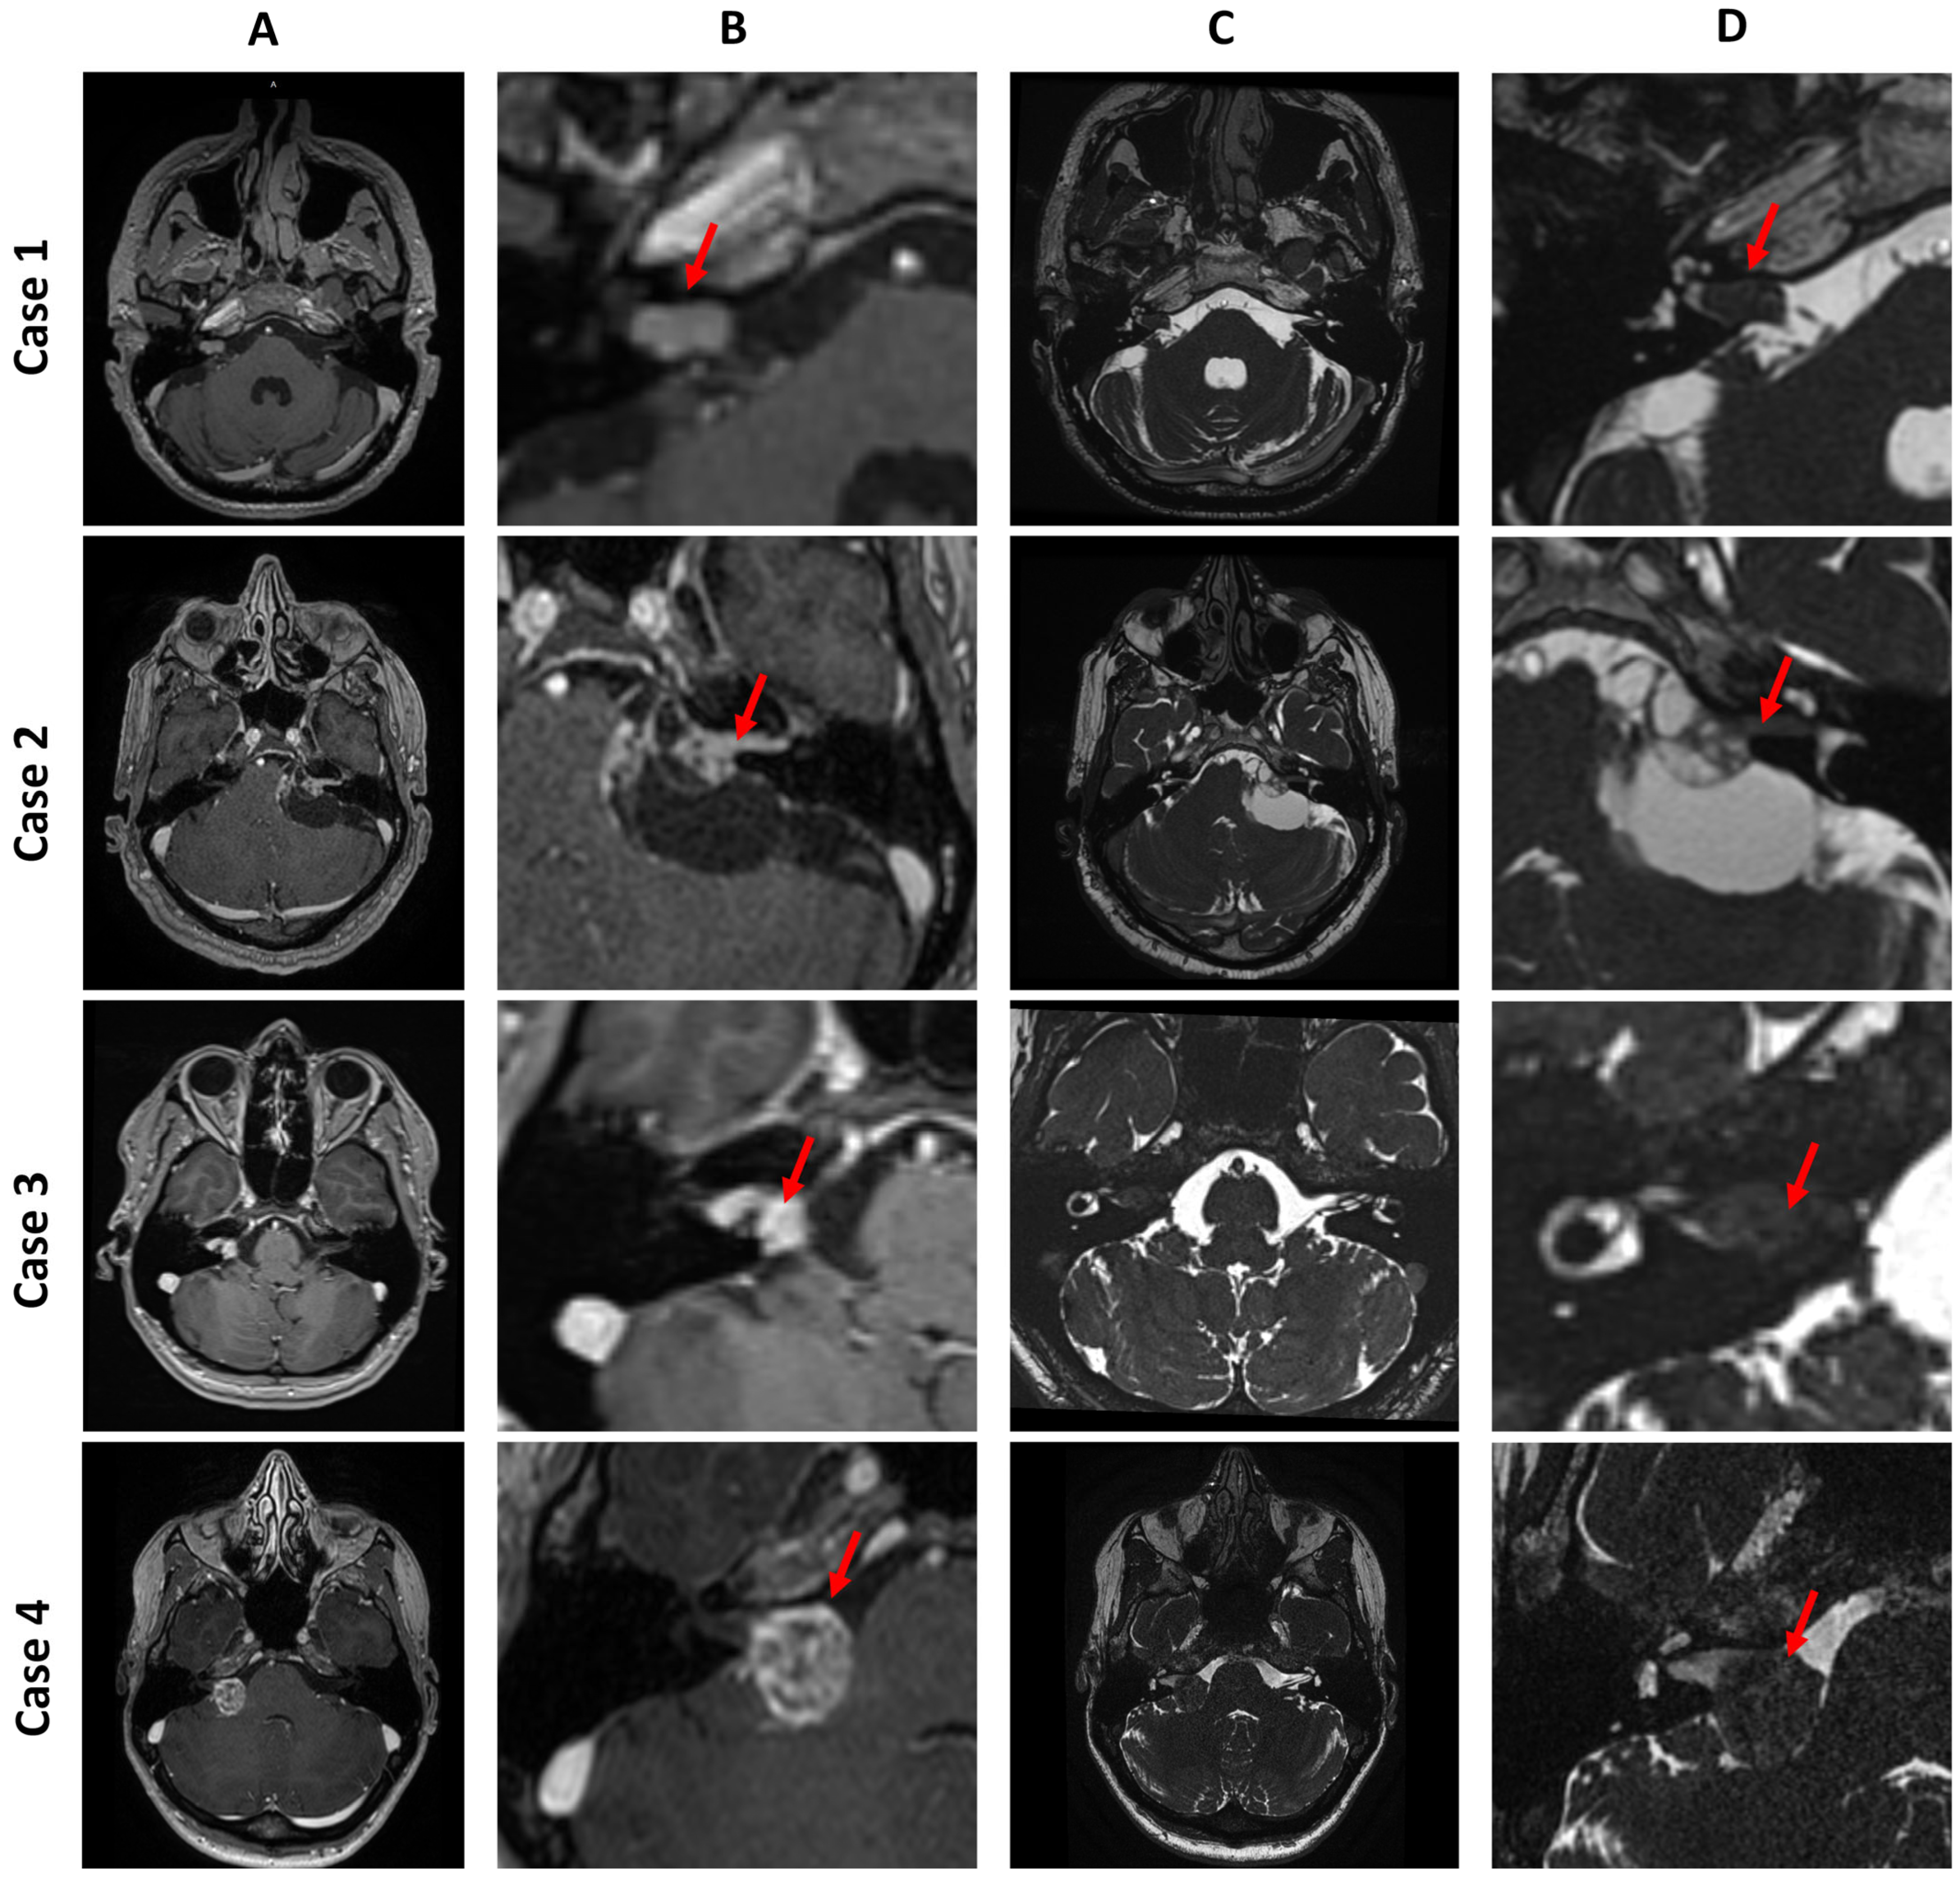

- Case 1 is a Koos I intracanalicular vestibular schwannoma in the right internal acoustic meatus with CSF cap separating the tumor from the cochlea.

- Case 2 is a Koos IV vestibular schwannoma with a cystic component in the left cerebellopontine angle, causing brainstem displacement.

- Case 3 is a Koos II vestibular schwannoma occupying the fundus of the right internal acoustic meatus and protruding into the cerebellopontine angle.

- Case 4 is a Koos III vestibular schwannoma present in the right cerebellopontine angle cistern, occupying less than half of the internal acoustic meatus.